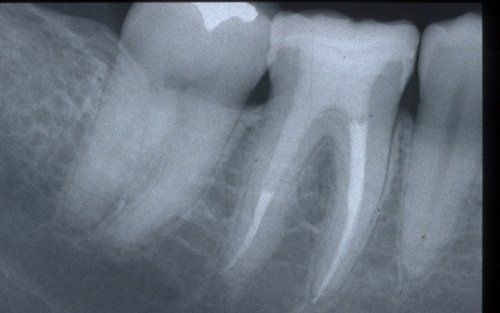

This treatment should be reserved for teeth that have irreversible pulp pathology (the nerve of the tooth) or an infection of the dental canals that has caused an abscess (acute apical periodontitis) or a granuloma (chronic apical periodontitis). While in the first two cases the tooth is very painful and the patient immediately seeks the dentist, the case of the chronic form is often silent, and therefore the patient may not notice anything for a medium to long period of time. In such conditions, it is only an X-ray image, taken during routine check-ups, that detects its presence. Root canal therapy can be completed by placing a latest-generation post inside the canal, as a means of retaining the material used for the reconstruction of the tooth. It will be up to the clinician to decide whether or not the restoration requires this additional anchoring system.